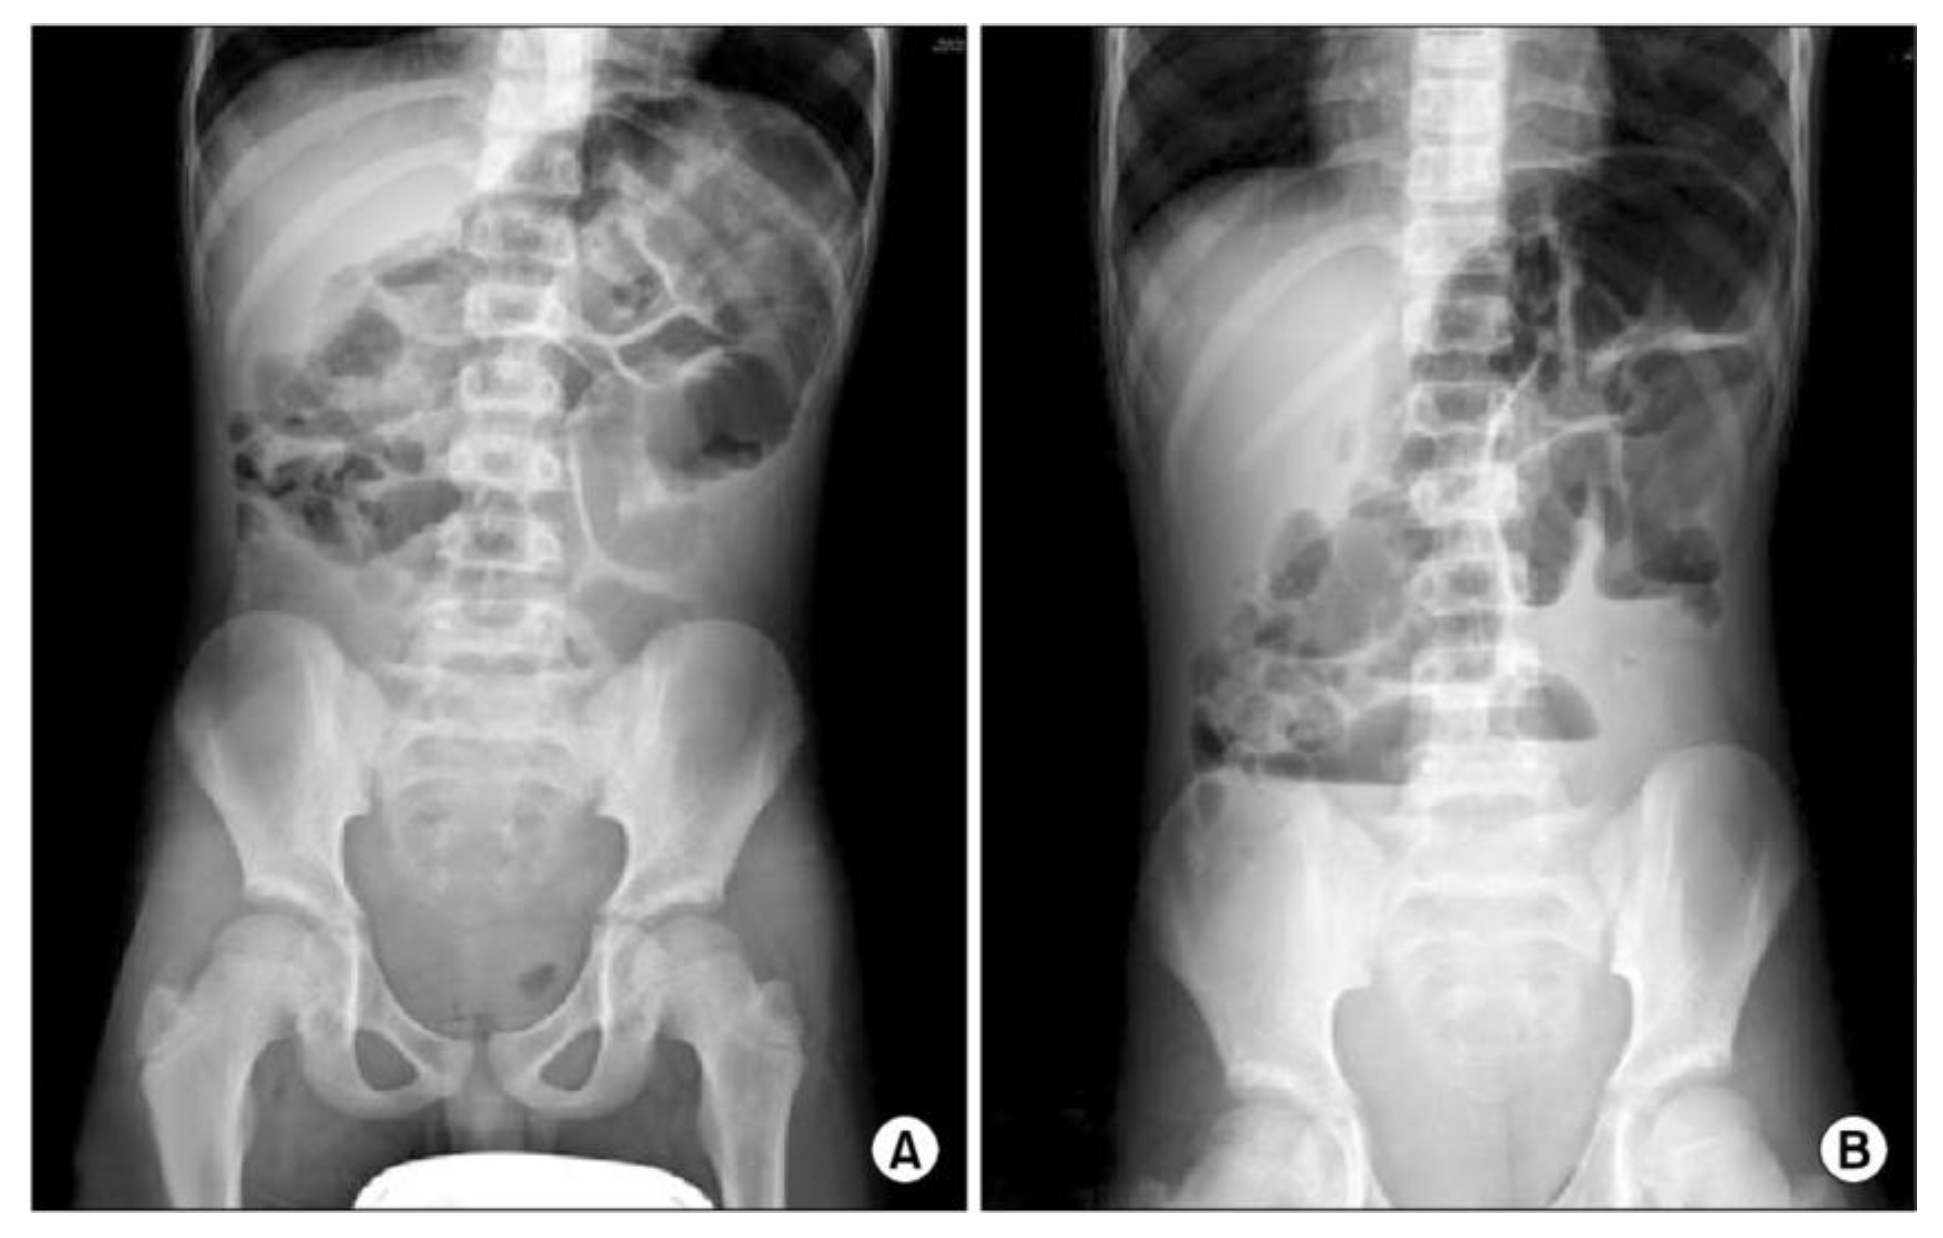

2. Case Presentation